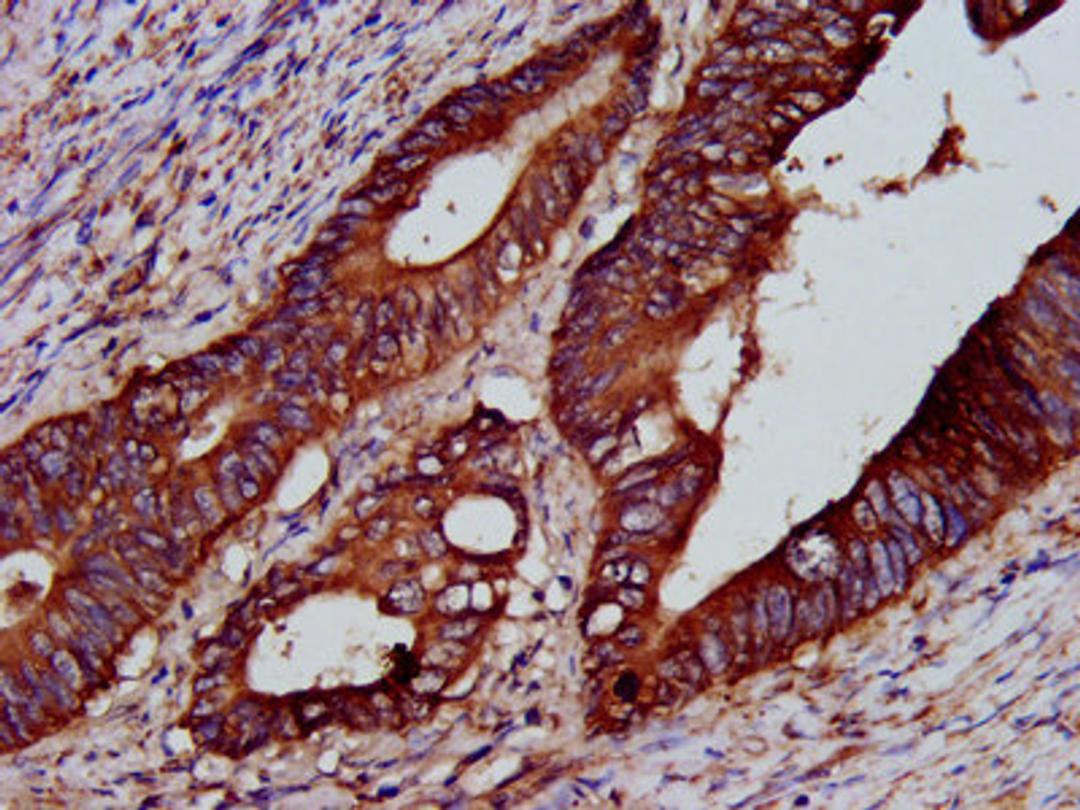

IHC image of CSB-PA613277LA01HU diluted at 1:200 and staining in paraffin-embedded human colon cancer performed on a Leica BondTM system. After dewaxing and hydration, antigen retrieval was mediated by high pressure in a citrate buffer (pH 6.0). Section was blocked with 10% normal goat serum 30min at RT. Then primary antibody (1% BSA) was incubated at 4°C overnight. The primary is detected by a biotinylated secondary antibody and visualized using an HRP conjugated SP system.